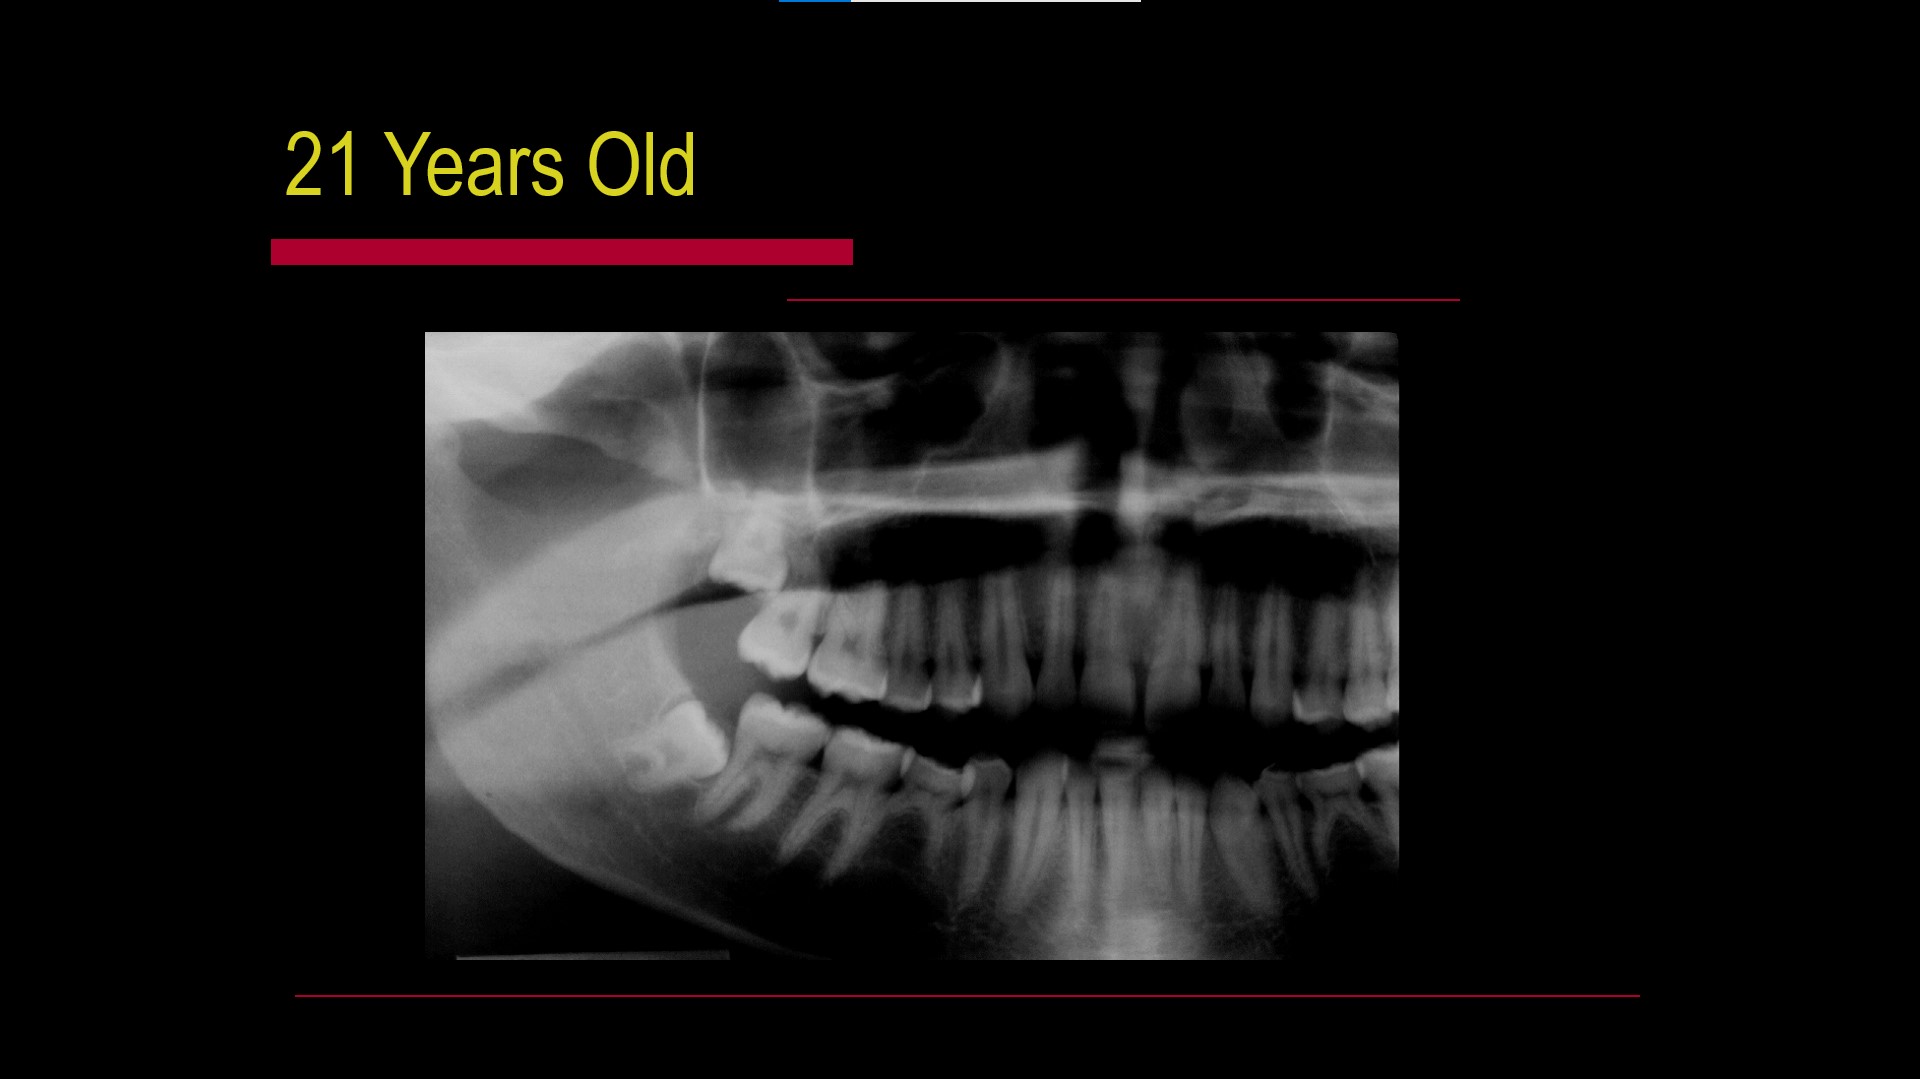

Impacted teeth